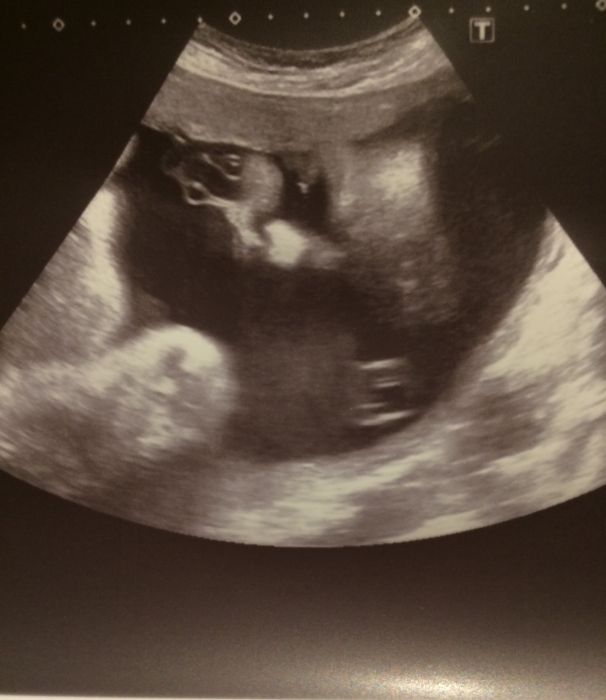

Holky, tak poslední velký utz dopadl výborně:-)potvrzena holčička, není už pochyb:-)...trvalo to asi 15 minut, všechno přeměřovali, odpovídá týdnům, cm nevím, to mi neřekli, ale váha je 1600g, neskutečně vyrostla! A jako velký bonus je, že placenta už není v porodních cestách, prý tak 2mm ve spodním segmentu, ale do porodu by se ještě měla vytáhnout tak bych měla snad rodit přirozeně, jupí!!! Jsem tak šťastná! Jo a je polohou podélnou hlavičkou, ale může se ještě přetáčet tak budu doufat, že skončí v téhle pozici:-). No a trochu se nám tam pletl pupečník, ale snad uvidíte obličej, je nádherná!

[1047866] Tuli, ani nevis jakou mam radost! Vidis, nakonec bude vsechno dobre. Jeste prezit ty pichance do prstu. A 1600g? Teda ta krasne roste. Jeste nedavno jsme resily par gramu a par milimetru... K tem fotkam by meli davat navod. Ale pri detailnim zkoumani se da neco najit :-)